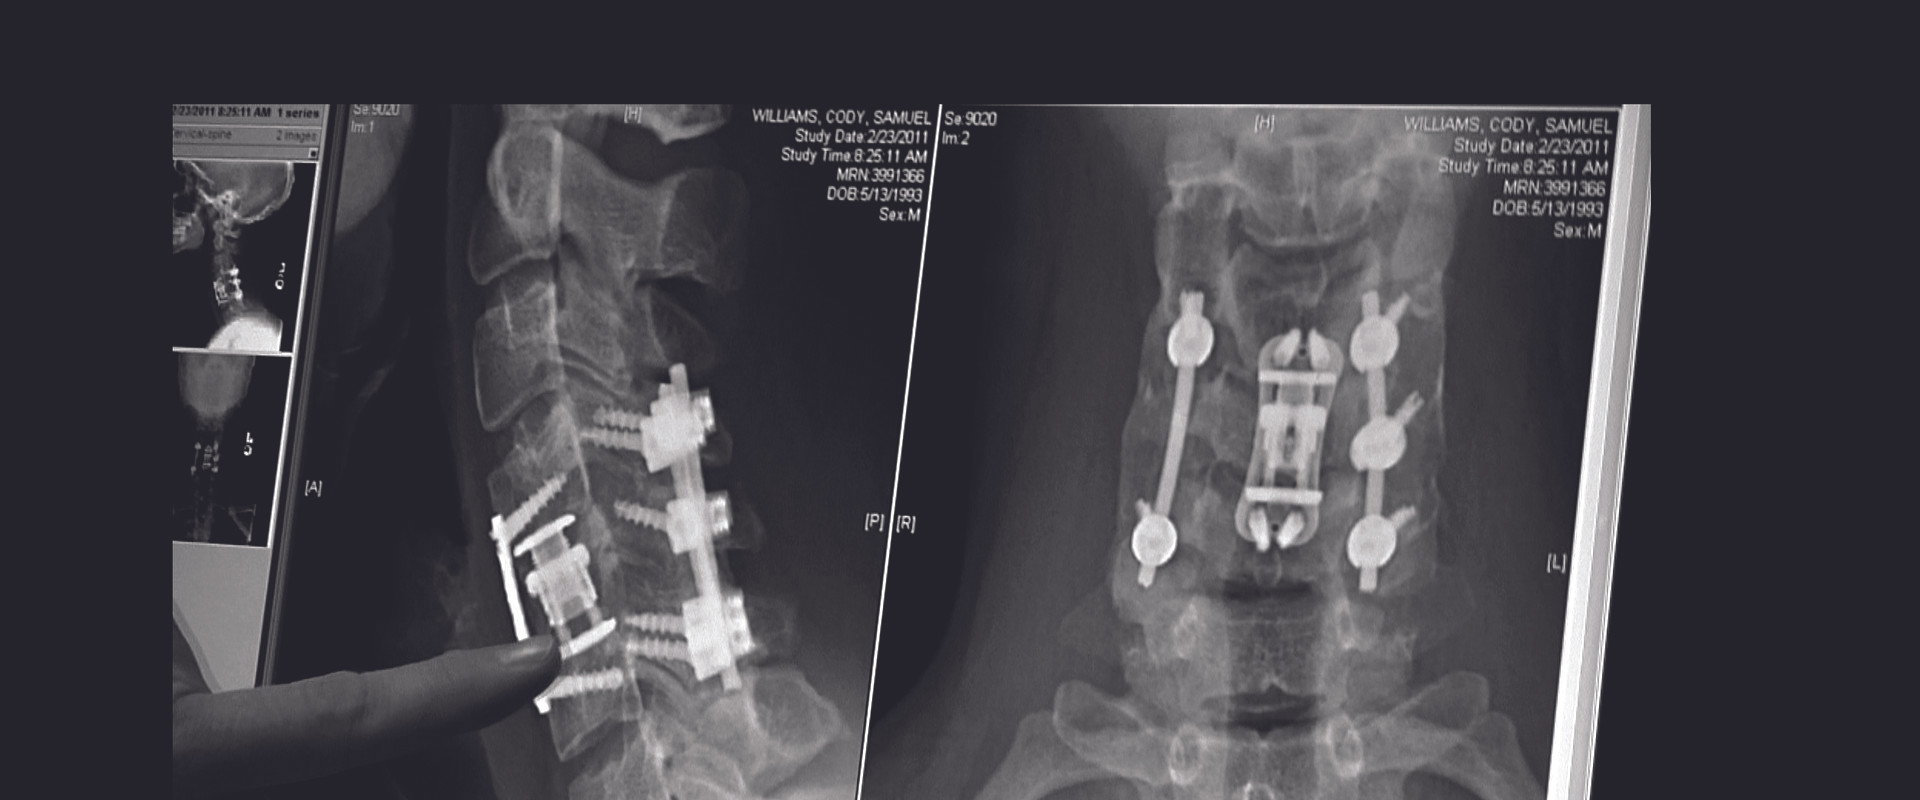

Cody Williams

Self